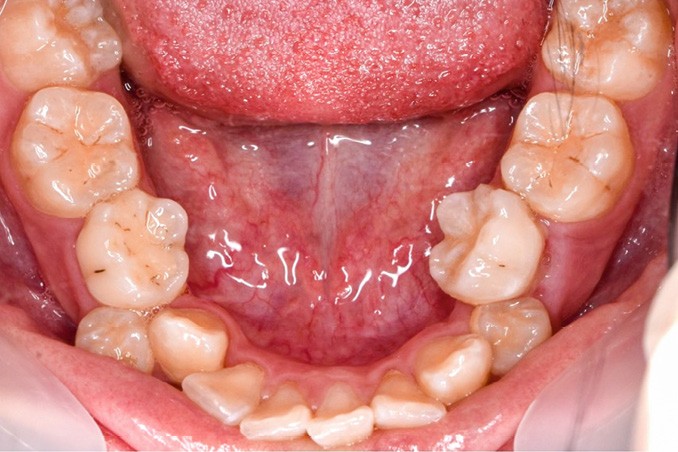

Une patiente âgée de 12 ans se présente en consultation, motivée par la position de son incisive centrale maxillaire, décrite comme « en avant », marquée par une dyschromie et une mobilité de grade 2 selon Muhlemann. L’examen clinique montre l’absence de 23 sur l’arcade, une dysharmonie dents-arcade marquée, un surplomb accentué, et une déviation des milieux inter-incisifs, conséquence du comblement spontané de l’espace de 23. L’ensemble s’inscrit dans un contexte de Classe I d’Angle molaire. L’orthopantomogramme révèle l’inclusion de 23, associée à une résorption radiculaire étendue aux deux tiers de 21. La 22 ne présente aucune altération visible.

La patiente, de profil normodivergent, présente une Classe I squelettique sans troubles fonctionnels (fig. 1-8).